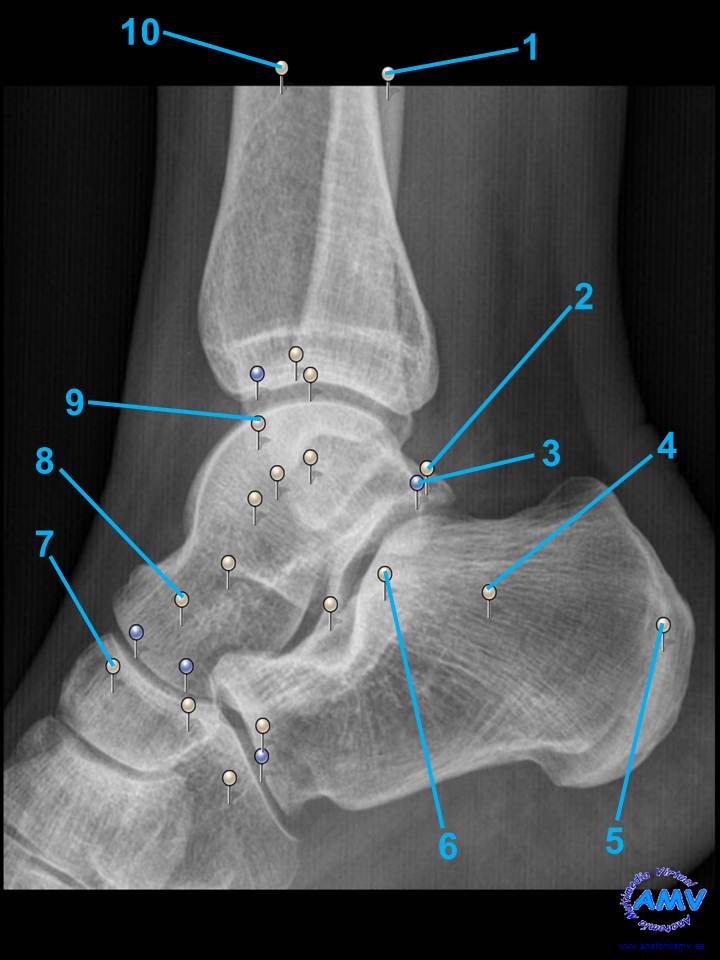

rx_mi_09.jpgIndique que estructura se señala con el número correspondiente:

El nº 1 señala .

El nº 2 señala .

El nº 3 señala .

El nº 4 señala .

El nº 5 señala .

El nº 6 señala .

El nº 7 señala .

El nº 8 señala .

El nº 9 señala .

El nº 10 señala .